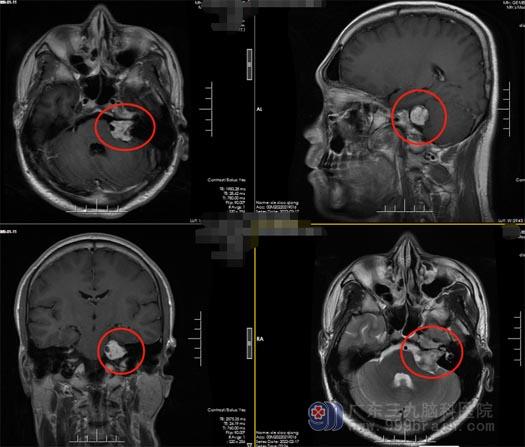

谢先生的爱人经多方打听,得知广东三九脑科医院神经外五科王国良团队是手术经验非常丰富的脑科团队,在广东三九脑科医院完善各项术前检查和准备工作后,由王国良主任主刀,在全麻下行“左侧桥小脑角听神经瘤切除术”,术中全切肿瘤,听神经、面神经保护完好,手术顺利结束。

▲术前